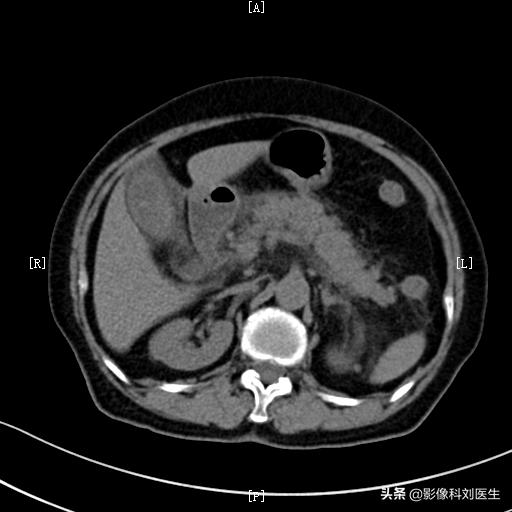

3、腹部CT检查。是诊断胰腺炎最重要的影像学检查。它可以观察胰腺肿大的情况,胰腺周围的渗出情况,通过三期增强扫描,可以判断胰腺组织内是否有坏死,周围是否有假性囊肿形成等。通过CT检查,可以明确急性胰腺炎的分型,了解其并发症情况,对其严重程度进行分级,所以是诊断急性胰腺炎的最佳方法。

急性水肿型胰腺炎:胰腺肿大,边缘毛糙,见多发条索影。

同一病人:胰周脂肪间隙模糊